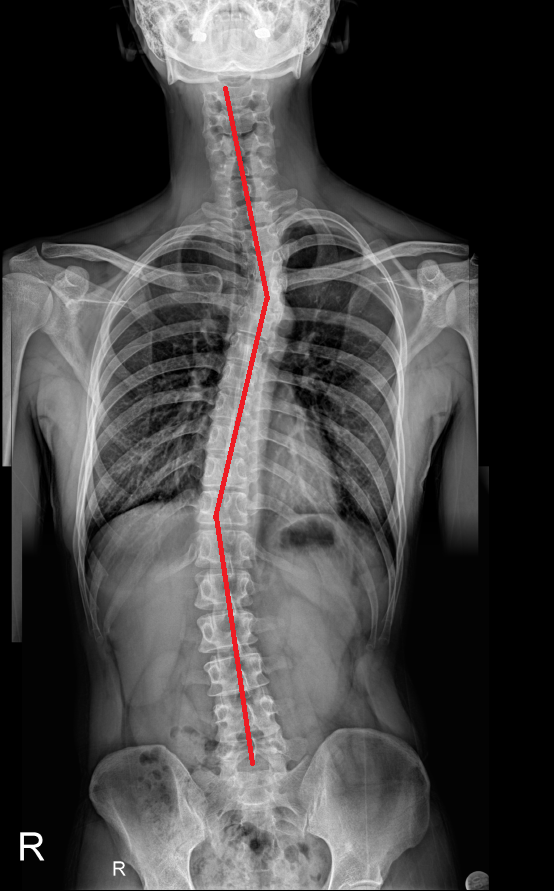

나는 척추측만증을 앓고 있다.

대략 16년 전에 척추측만증 판단을 받았다.

척추측만증 각도는 크게 변화가 없이 살다가 좋아지게 된 계기가 있었다.

그랬더니 견갑골의 위치가 어느 정도 돌아오면서 척추의 각도와 견갑골의 위치가 이전 보다 눈에 띄게 좋아졌다.